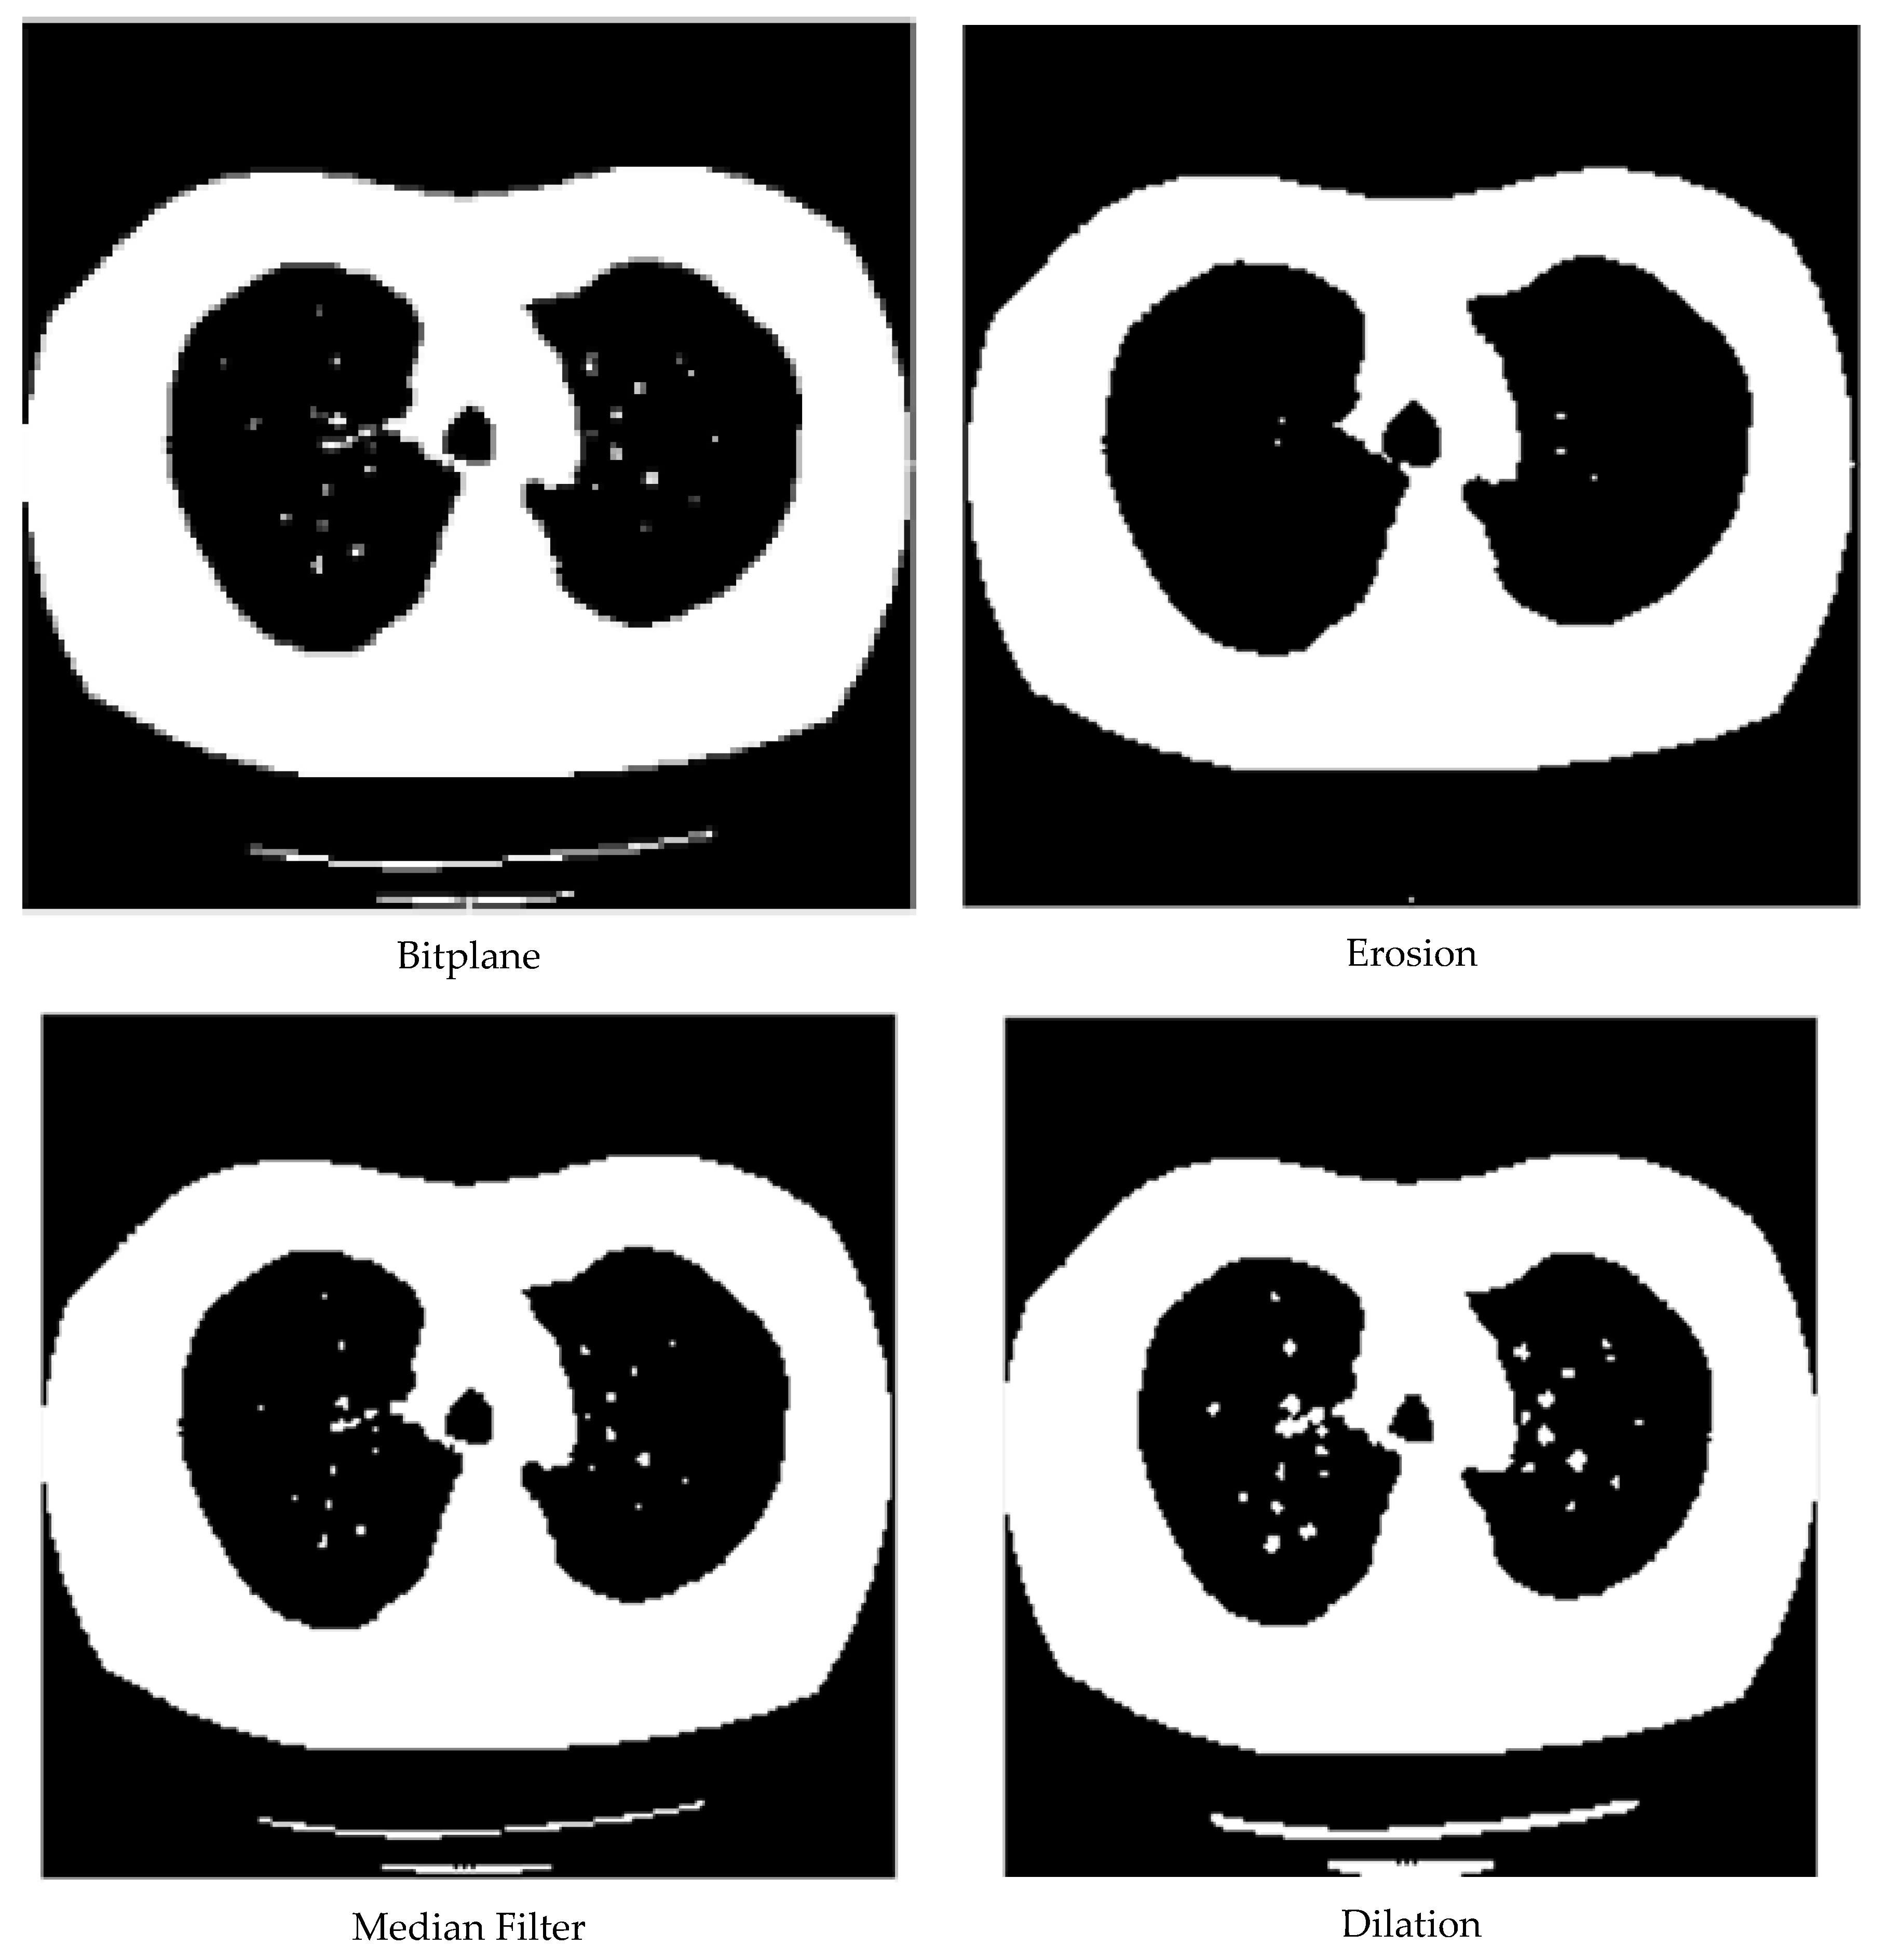

3.1. Data Pre-Processing